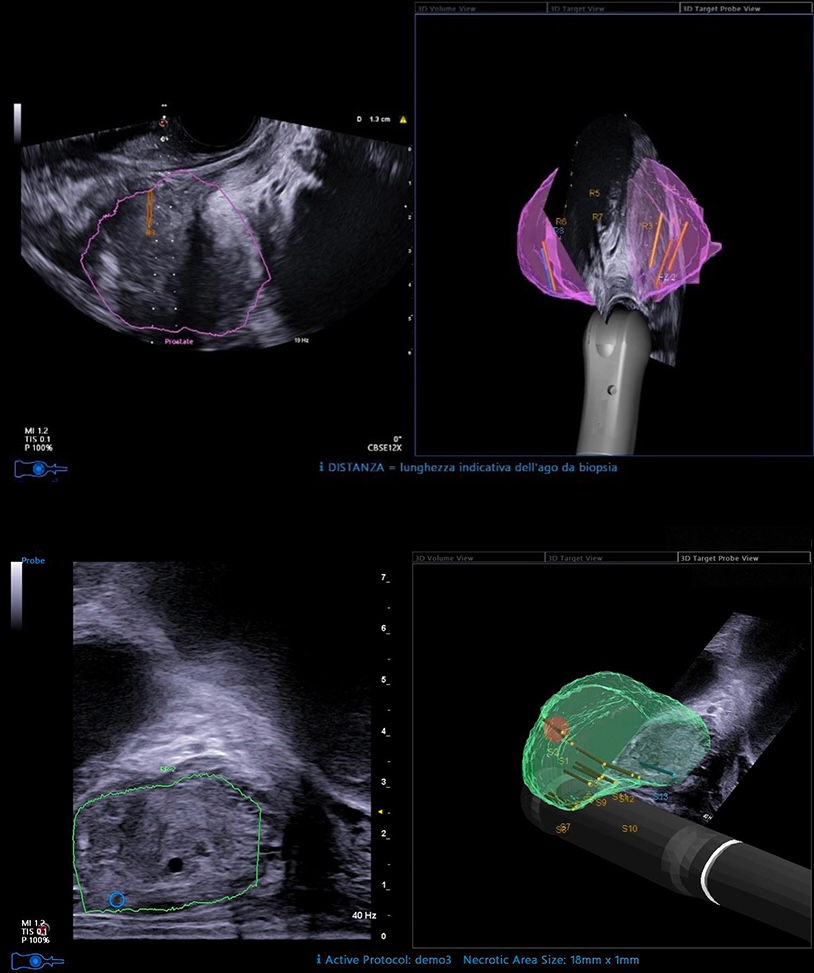

Au sein du cabinet d'urologie à Lille et Marcq en Barœul, la biopsie de prostate est guidée par échographie à l’aide du système Esaote et de son module UroFusion.

Ce dispositif permet de fusionner les images IRM et échographiques en temps réel, offrant un repérage précis des zones suspectes identifiées sur l’IRM prostatique.

Chaque prélèvement peut ainsi être ciblé avec une grande fiabilité, améliorant la détection des cancers significatifs et limitant les prélèvements inutiles.

Lorsque cela est nécessaire, ou que cela peut apporter un interêt, les images IRM sont relues et analysées avec l’appui de la plateforme Quibim Precision (QP), un outil d’aide à la décision basé sur l’intelligence artificielle. Cette analyse renforce la standardisation et la qualité du diagnostic.